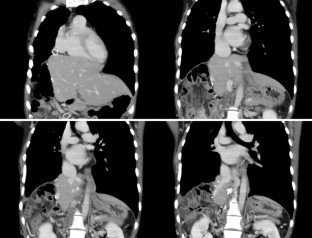

Fig. 2